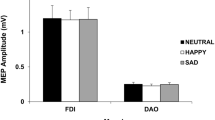

It could be ascertained by camera monitoring that all the subjects performed the lip protrusion task perfectly and symmetrically. The BOLD signals data analysis with Brain Voyager showed that the sensorimotor cortex was activated strongly and widely in all the subjects. No significant activation in Broca’s or Wernicke’s areas was observed. Table 1 shows the summary of the number of activated voxels in the sensorimotor cortex at a corrected P < 0.001 by the multiple comparison method, and the Talairach coordinates at the most active regions. In men, the results of individual data analysis revealed a larger number of activated voxels in the left sensorimotor cortex than that in the right, and there was a statistically significant difference in the number of activated voxels between in the left and the right side (Wilcoxon signed rank test, P = 0.0051) (Fig. 1). On the other hand, no significant difference was found between the left and right side in women (Fig. 2). There was a statistically significant difference in interaction between the hemisphere and sex (Two-factor factorial ANOVA, P = 0.041) and multiple comparison test showed statistically significant differences between “men and right” and “men and left”, and between “men and left” and “women and left” (Fisher’s PLSD method, P = 0.018, 0.026, respectively). The results of group data analyses indicated bilateral strong activation of the sensorimotor cortex during lip protrusion at an uncorrected P < 3.1294 e−12 level (corrected P-values could not be seen in the statistical maps; i.e, P < 0.000) by the multiple comparison method (Bonferroni’s correction) (Figs. 3 and 4). In general, the cluster size of the activated area in the group data analysis was larger than that in the individual data analysis because of the averaging of each individual data set. The areas of activation on the left side were larger than those on the right side in men, though no significant laterality was observed in women. Activation in the bilateral supplementary motor cortex and cerebellum was also observed, but no laterality was found (Wilcoxon signed rank test, P > 0.05, respectively). Detailed analysis of the averaged time-course of changes in the BOLD responses for the ROIs in the sensorimotor cortex revealed that the peak %BOLD signal in the left sensorimotor cortex was approximately twice as large as that in the right in the male group (Fig. 3), although no laterality was found in the female group (Fig. 4). In detail, the peak value of the percent changes in BOLD signals for the right sensorimotor cortex was approximately 0.5, whereas it was 1.2 for the left in men. In a GLM (multi-study, multi-subject) analysis, the left primary sensory area was significantly activated (yellow), though the right one was not activated (right, Fig. 5). A cluster center of spatial gravity was evaluated at the Talairach coordinate sets (−51, −22, 36) corresponding to the primary sensory area related to the face area. On the other hand, green regions were also activated as brain regions where female activation was greater than male. A cluster center of the left hemisphere green region near the yellow one was evaluated at the Talairach coordinate sets (−40, −21, 42) and that of the right one was (47, −19, 44). Statistical analysis of data in the group study and the male and female characteristics (mean age, laterality quotient, past history of facial nerve diseases or cerebrovascular diseases) are shown in Table 2. There was no statistically significant difference in the R/L amplitude ratio of the facial muscle action potential between men and women as shown in Table 2.

Comparison of the mean number of activated voxels in the left and right sensorimotor cortices in men. There is a statistically significant difference in the mean number of activated voxels between the left and the right sides (Wilcoxon signed rank test, * P = 0.0051). (Error bars indicate one standard error)